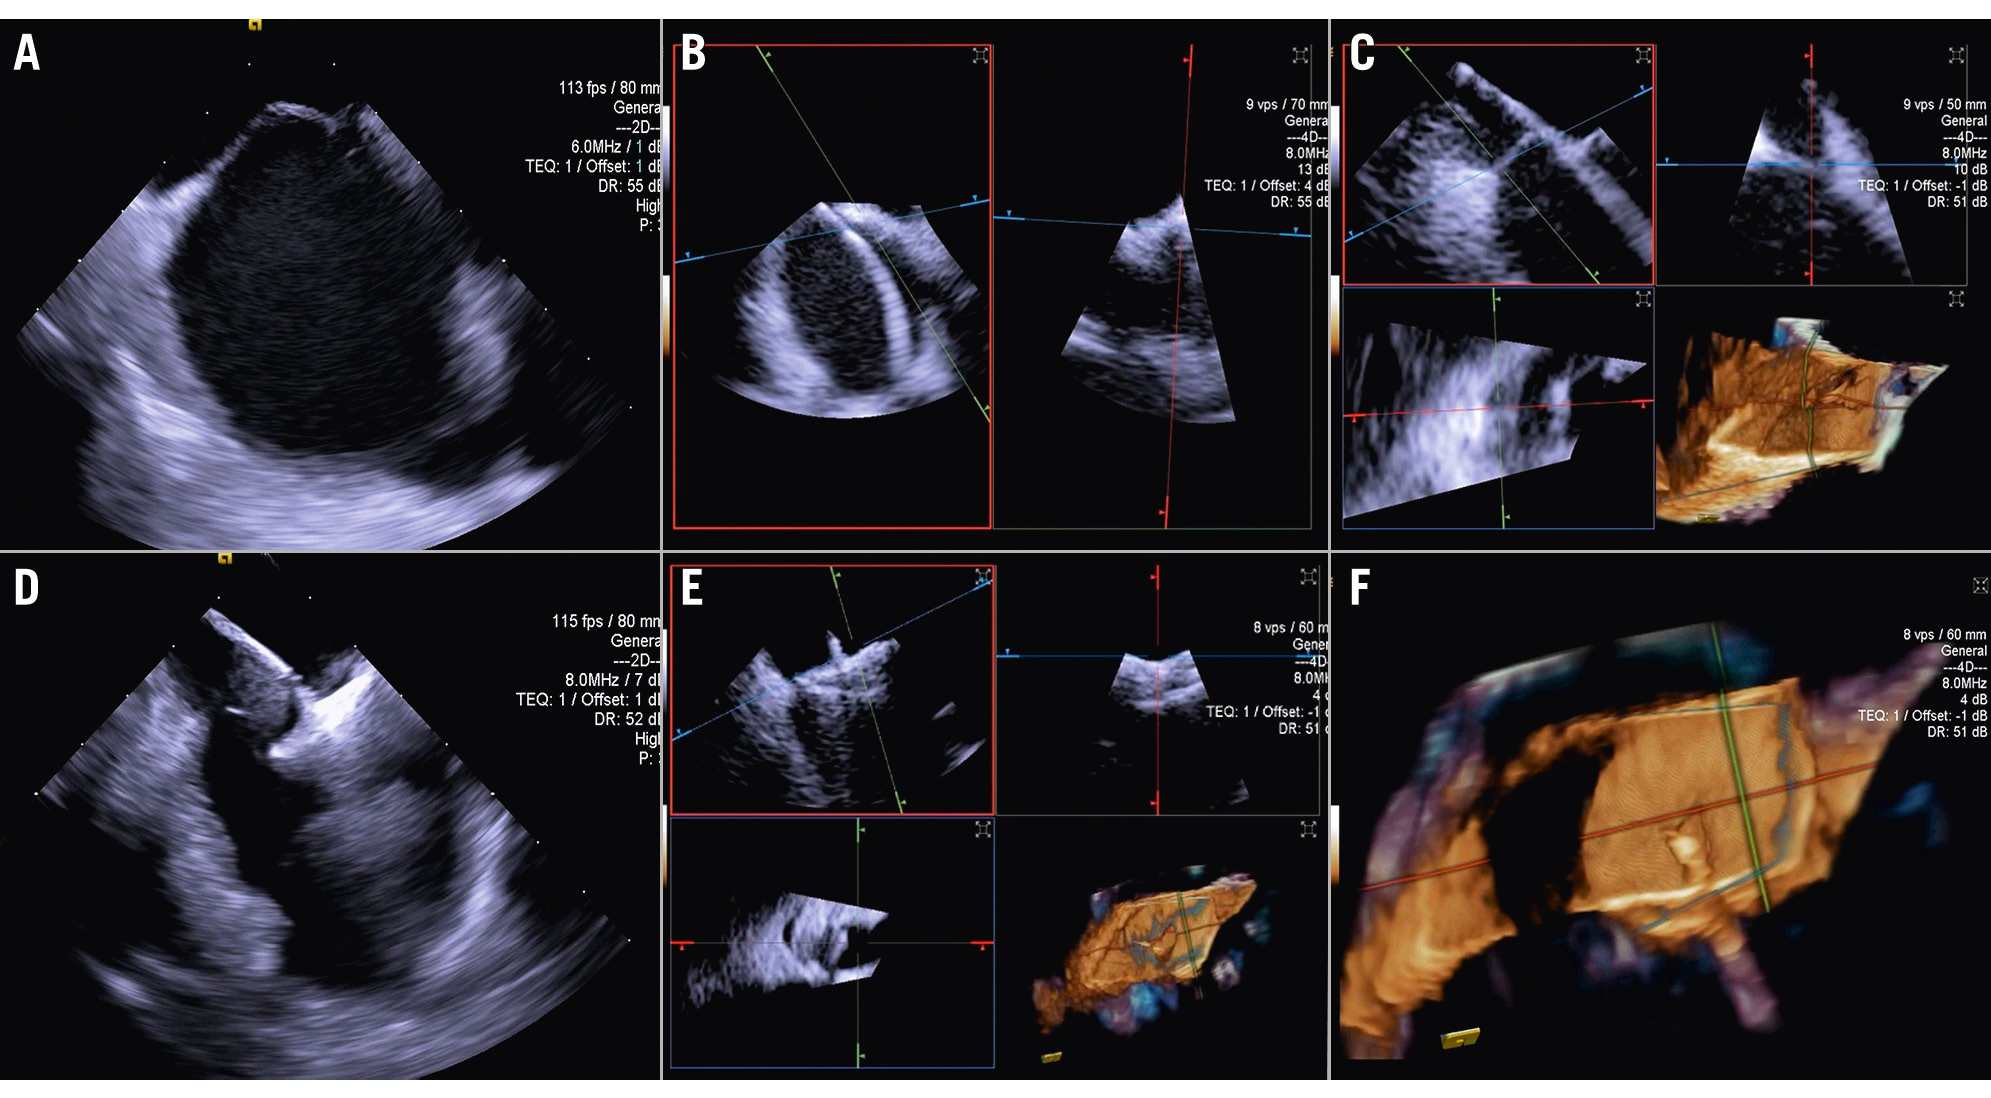

Central illustration. Current landscapes on 3D ICE utilisation. An overview of the key structural heart interventions that increasingly utilise 3D ICE: (A) mitral TEER/ViV; (B) IAS defect/ PFO closure; (C) Tricuspid TEER/TTVR; (D) LAAO. E) An illustration of the ICE probe’s position during imaging of the tricuspid valve. F) An illustration of the ICE probe’s position during imaging of the mitral valve. 3D: three-dimensional; ICE: intracardiac echocardiography; IAS: interatrial septum; LAAO: left atrial appendage occlusion; TEER: transcatheter edge-to-edge repair; TTVR: transcatheter tricuspid valve replacement; ViV: valve-in-valve

For other procedures, such as transcatheter TV repair or replacement, 3D ICE is typically complementary to TOE16. TOE is the gold standard for TV imaging, but as previously noted, the posterior positioning of the probe relative to the valve can result in far-field tangential views with acoustic shadowing from other heart structures. Given its insertion via the femoral vein and ease of positioning within the right atrium (RA), the 3D ICE probe provides enhanced visualisation of the tricuspid leaflets and annulus (Figure 1, Moving image 1). Nevertheless, it is important to note that despite these advantages, 3D ICE imaging cannot entirely replicate all TOE views, particularly the transgastric short- and long-axis views, underscoring the ongoing clinical utility of TOE in numerous scenarios17. However, this may change in the future, depending on the imaging needed for a specific TV prosthesis implant.

Figure 1. Three-dimensional reconstruction of the atrial view of the tricuspid valve.

When performing a tricuspid TEER procedure (TriClip [Abbott], PASCAL [Edwards Lifesciences]), shadowing from mitral/aortic prostheses, septal hypertrophy, and other factors are particularly problematic when assessing for leaflet insertion. Three-dimensional ICE is a useful alternative for leaflet insertion in edge-to-edge repair. Starting from the home view (right ventricular inflow view), the use of biplane imaging creates a potential grasp view. Subsequently, a live 3D volume image can be obtained and used for a live 3D MPR16. Similar to TOE, 3D ICE also can be used for trajectory and alignment (Figure 4, Moving image 2-Moving image 3-Moving image 4-Moving image 5-Moving image 6-Moving image 7).

Figure 4. Three-dimensional ICE-guided tricuspid transcatheter edge-to-edge repair. A) 3D MPR ICE imaging planes with posterior and anterior leaflets in the TV home view (top left), septal leaflet and anterior/lateral grasping view (top right). The blue plane (bottom left) represents the short-axis (atrial en face) view of the TV leaflets. Finally, the corresponding 3D volume (bottom right; the aorta is at 5 o’clock). B) 3D colour MPR ICE imaging shows severe tricuspid regurgitation, allowing assessment of the number of regurgitation jets and jet location. C-E) The first device is advanced under the tricuspid valve. Clip orientation is optimised to be orthogonal to the coaptation line while the clip position is fine-tuned to the target location, and independent leaflet grasping is performed. F) 3D MPR assessment of second device orientation and location. G) 3D MPR assessment of third device orientation and location. H, I) 3D MPR and colour-flow Doppler final assessment of the devices. 3D: three-dimensional; ICE: intracardiac echocardiography; MPR: multiplanar reconstruction; TV: tricuspid valve